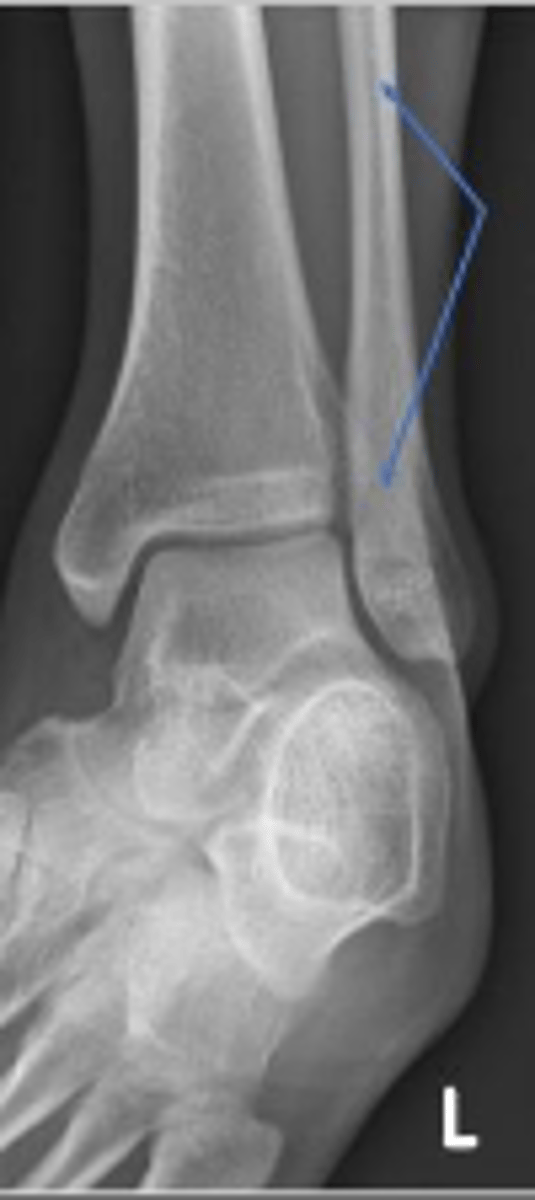

Axial relationship of the ankle

What is the overarching name of the assessment?

Tibial angle & fibular angle

What are the 2 components of the assessment?

Fibular angle

What is the name of the assessment?

Yes

Is the assessment within normal limits?